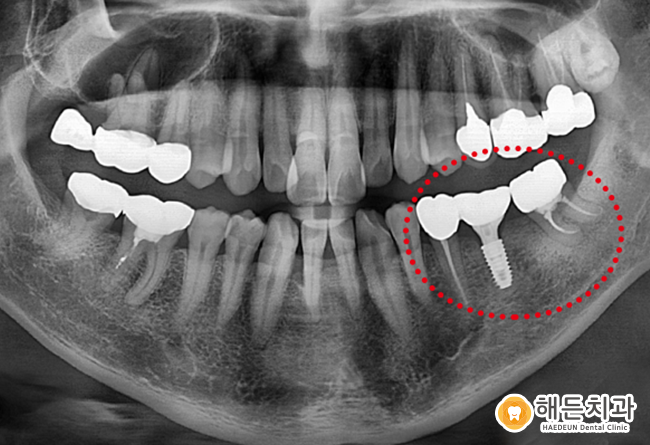

신경치료와 임플란트 식립 과정을 거친 뒤,

최종 단계로 보철물을 장착한 모습입니다.

초기 진단부터 계획 수립까지의 과정을 바탕으로

해든치과에서 전체 치료가 마무리되었으며,

현재는 기능적인 회복과 외형적인 부분까지 함께

고려된 상태를 확인할 수 있습니다.

처음 임플란트를 경험하신 환자분께서도

치료 이후 일상적인 사용에 대한 적응 과정에서

비교적 자연스럽게 느껴진다고 말씀해 주셨으며,

전반적인 치료 과정에 대해

긍정적인 반응을 보이셨습니다.